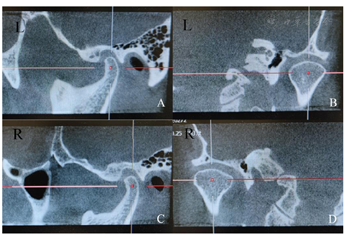

双侧颞下颌关节及咀嚼肌区域无压痛,双侧颞下颌关节无弹响,开口度、开口型正常;

方圆面型,面部左右对称,双侧咬肌肥厚,面下1/3比例偏低,不戴

垫时面下距离66mm,戴

垫时68mm。